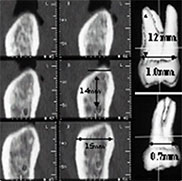

CT사진에서 삼차원 상을 구성해서

복제치아를 만드는데 이용함

복제치아를 이용해서 옮겨질 뼈의 모양을 다듬고

발치하자마자 가급적 빠른시간내에 이식함